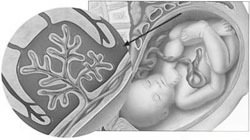

Патология плода у беременных

Курящая женщина подвергает своего будущего ребёнка серьёзному риску. Доказано, что у интенсивно курящих женщин рождаются дети с низкой массой тела. Составляющие сигаретного дыма, попадая в кровь беременной женщины, снижают насыщаемость крови кислородом, что неизменно ведёт к гипоксии – кислородному голоданию плода. Существенно нарушается плацентарное кровообращение: обмен питательных веществ между кровью матери и кровью плода. Выкидыши, преждевременные роды, мёртворождения – удел многих мам, которые не находят в себе сил расстаться с сигаретой. Врождённые пороки развития и уродства плода — частое следствие курения на ранних сроках беременности. Иммунитет деток, рождённых курящими мамами, заметно снижен, синдром ВМС (внезапной младенческой смерти) встречается чаще.